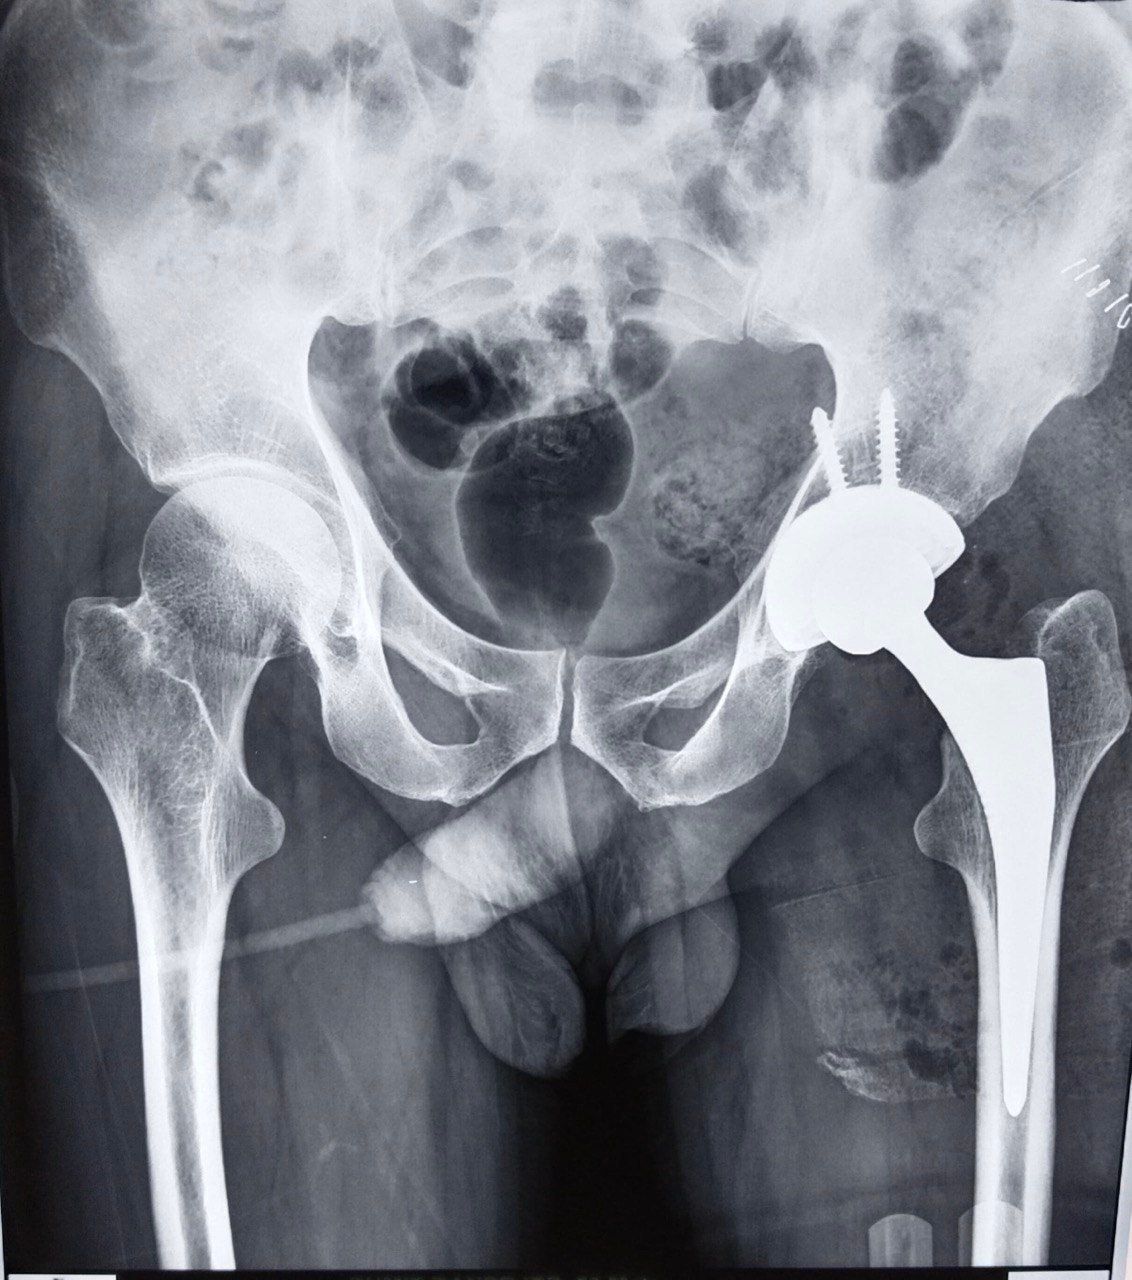

Garden Type IV Fracture Neck of Femur

Post-Op X-Ray